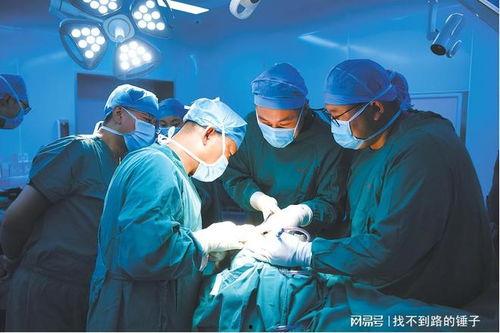

话说那天,佛山某口腔医院的一则视频在网络上迅速走红。视频中,一位患者痛得满头大汗,而医生却似乎并不在意,还在继续操作。这一幕被患者家属用手机记录下来,随后上传到了网上,瞬间引发了网友们的热议。

视频中,患者躺在手术台上,面部表情痛苦,嘴里插着牙具。医生则在一旁操作,似乎并没有注意到患者的痛苦。更有甚者,视频中还出现了医生在手术过程中玩手机的情况。这一幕让不少网友纷纷表示:“这医生也太不专业了吧!”

面对网友的质疑和热议,佛山这家口腔医院迅速做出了回应。医院表示,视频中的情况并非医疗事故,而是医生在为患者进行常规的口腔检查。至于医生玩手机,医院解释称,当时医生正在查看患者的病历,并非在玩手机。